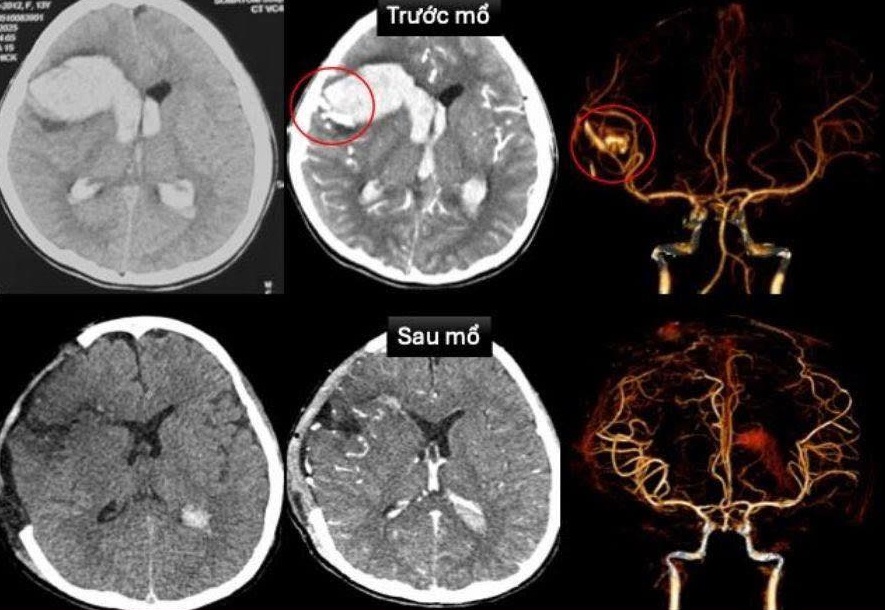

Hình ảnh mạch máu não bị vỡ do dị dạng. Ảnh: BVCC. |

Kết quả cho thấy vỡ dị dạng động, tĩnh mạch trán phải gây xuất huyết lan rộng trong nhu mô và não thất. Cùng lúc, siêu âm tim phát hiện bệnh cơ tim xốp, khiến tim co bóp yếu và dễ rối loạn nhịp.

Bác sĩ chuyên khoa Tim mạch nhanh chóng can thiệp, đặt máy tạo nhịp tạm thời nhằm kiểm soát rối loạn nhịp và duy trì hoạt động của tim. Cùng lúc, ê-kíp Ngoại thần kinh tiến hành mở sọ giải áp cấp cứu, loại bỏ phần mạch máu dị dạng bị vỡ và lấy hết khối máu tụ chèn ép trong não để giảm áp lực nội sọ và cứu não bộ của bệnh nhi.

Sau hơn 3 tuần, bé T. tỉnh táo, nhận biết được, chỉ còn yếu nhẹ chân phải. Kiểm tra MRI sọ não sau mổ cho thấy không còn dị dạng mạch máu, trong khi siêu âm tim ghi nhận chức năng co bóp tim phục hồi tốt (EF 65%). Bé T. đã xuất viện trong tình trạng ổn định.